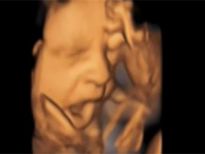

Bebeğin esneme anı

Bilim adamları bebeklerin ana karnındaki gelişimlerini daha iyi gözlemleyebilmek için ilginç bir deney yaptı. 15 anne adayının üzerine 4D ultrason sistemini kullanarak bebeklerin anne karnında ultrasonlarını çektiler. Çeşitli açılar ve teknikler kullanılarak yapılan bu yöntem normal ultrasonun aksine daha detaylı bir görüntü sağlıyor.